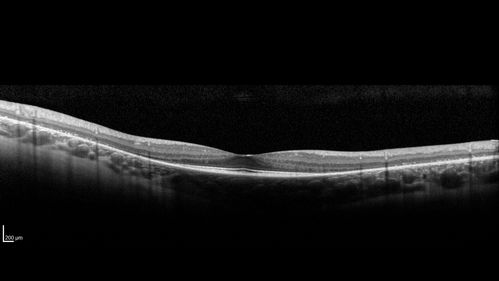

Retinitis Pigmentosa - Simplex - 16 year old female good vision

Difficulty with night vision

No family history

VA 20/25 OD, 20/16 OS

Negative for RPE65